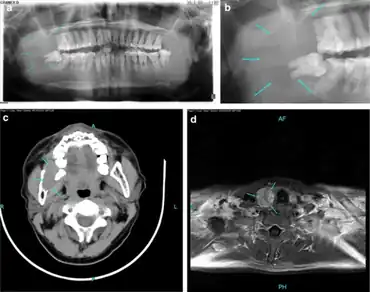

- ↑ EL-Sobky TA, Ahmad KA, Samir S, EL Mikkawy DME (2016). "Primary hyperparathyroidism in a child: The musculoskeletal manifestations of a late presenting rare endocrinopathy". Egypt J Radiol Nucl Med. 47 (4): 1613–16. doi:10.1016/j.ejrnm.2016.09.002.